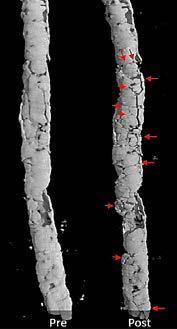

JM: For this study, we used a bank of donated arteries, characterized them mechanically, and imaged them with micro-CT. There were a variety of lesions, from total occlusions to no occlusions with circumferential calcium. We created conditions as close as we possibly could [to a living vessel] on the bench, fully mounting the artery into a module, and then putting it into the micro-CT without disturbing how the artery is stretched or twisted. We treated a number of popliteal and tibial vessels, and found that what people like Dr. Tahara were seeing in the hybrid operating rooms and cath labs—that there is some sort of action occurring on the calcium—was, in fact, occurring. It didn’t happen in all of them, but it was very interesting to compare these pretreatment and post-treatment vessels and see new cracks in calcium from the laser.

(1) Zilver (Cook Medical) stent under CTA (top) versus micro-CT (bottom). Images courtesy of Alexey Kamenskiy, UNO Biomchanics; (2) Pre- and post-Auryon micro-CT of calcification in a posterior